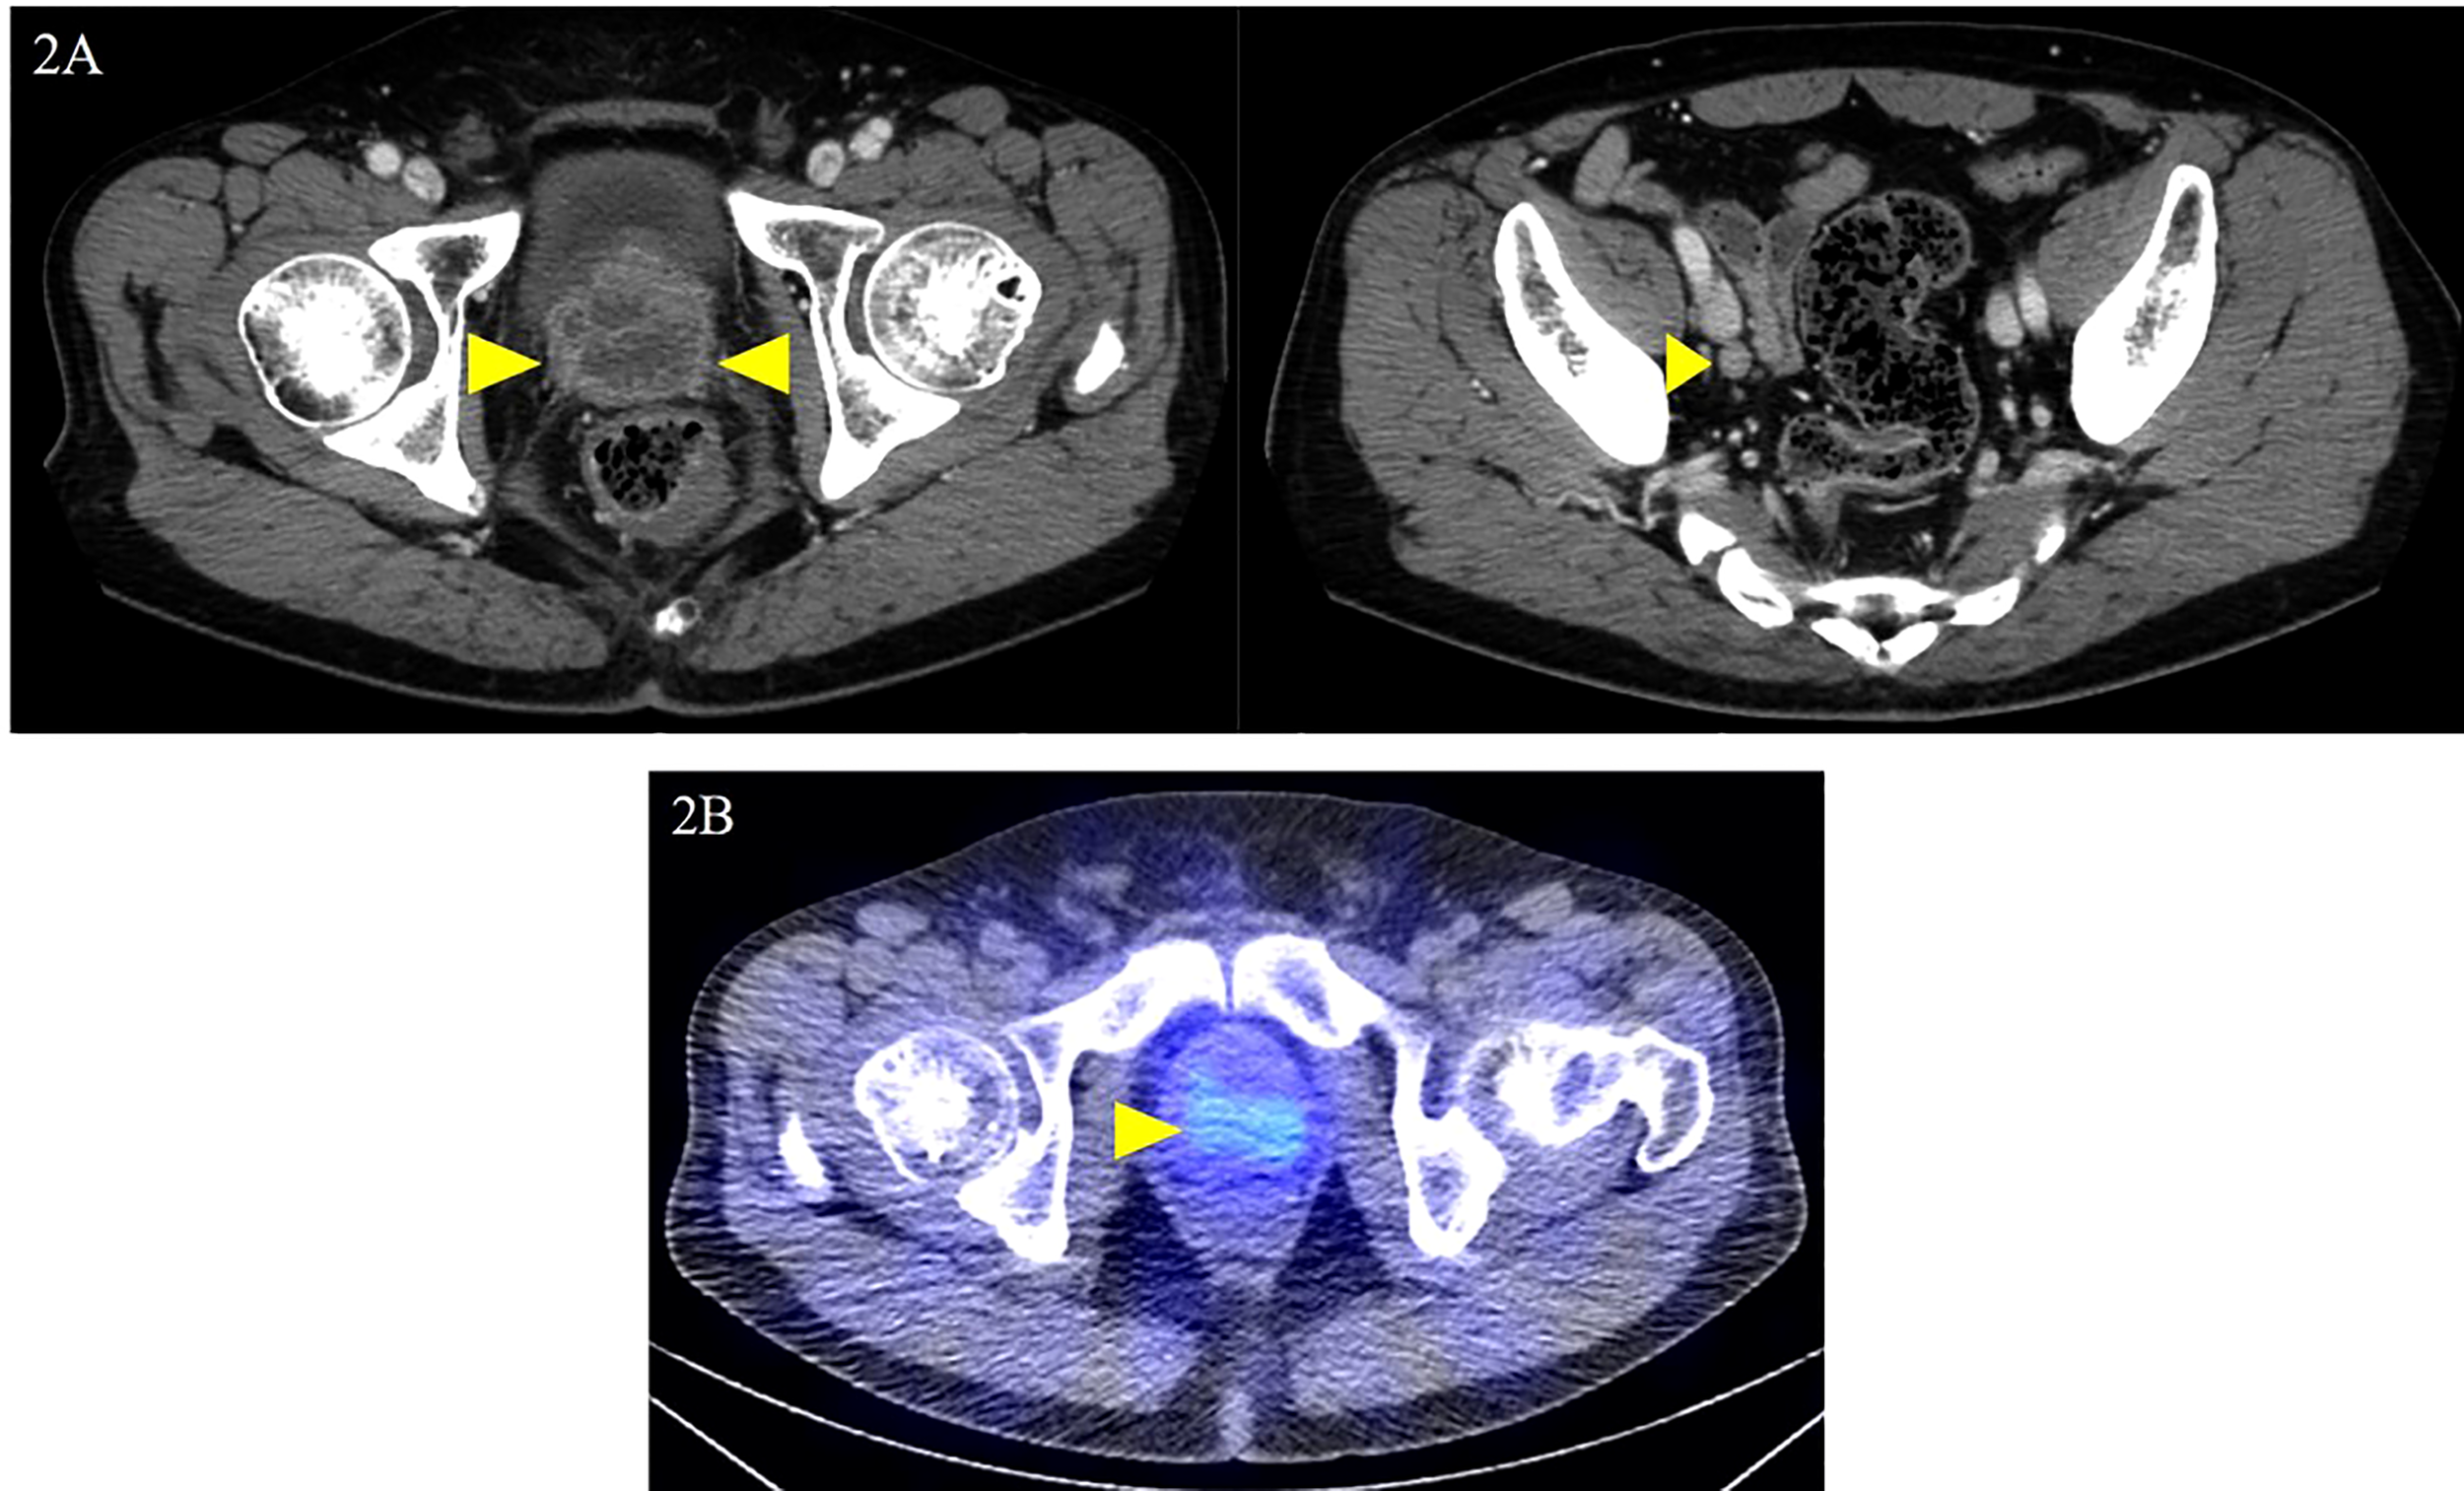

The patient was diagnosed with cT3aN0M1c (PUL) prostate cancer, and combined androgen blockade (CAB) with bicalutamide and degarelix was administered. In August 2019, the PSA decreased to 1.151 ng/ml, but it rose again to 3.800 ng/ml in November 2019, and the patient was referred to our hospital for further treatment. Serum PSA, neuron-specific enolase (NSE), and progastrin-releasing peptide (proGRP) were present at high levels at the first visit to our department with values of 4.220 ng/ml, 24.3 ng/ml (<16.3 ng/ml), and 206 pg/ml (≤75 pg/ml), respectively. Serum testosterone was at a castration level of 0.05 ng/ml. Contrast-enhanced computed tomography (CECT) showed an irregular contrast effect over the entire prostate, and somatostatin receptor scintigraphy showed mild accumulation in the prostate (Figure 2). After changing from degarelix to leuprorelin acetate, a prostate re-biopsy was performed in December 2019, and small cell carcinoma was detected (Figure 3). The patient had metastatic CRPC-NE and was treated with etoposide plus cisplatin (EP) (etoposide, 100 mg/m2/day, days 1–3; cisplatin, 80 mg/m2/day, day 1, repeated every 3 weeks). After the first EP course, renal function declined, so cisplatin was replaced by carboplatin (CBDCA) with a total of two courses of etoposide plus CBDCA (etoposide, 80 mg/m2/day, days 1–3; CBDCA: AUC 5, day 1, repeated every 4 weeks). This was followed by irradiation of the prostate region (external beam radiation therapy, 70 Gy, 35 fractions). However, after completing irradiation, the patient complained of perineal pain and pain during urination, and CECT showed recurrent prostate staining, lymph node metastasis, and de-novo pancreatic metastasis. Two courses of single agent CPT-11 (100 mg/m2/day, days 1, 8, and 15, repeated every 5 weeks) were administered as salvage chemotherapy, and concurrent MSI was investigated. MSI status was investigated using an approved kit (MSI‐IVD kit, FALCO biosystems, Kyoto, Japan). The analysis of prostate re-biopsy specimens showed a high MSI status, and the patient was given pembrolizumab (200 mg/day, day 1, every 3 weeks). Following pembrolizumab administration, the local prostate, lymph node, and pancreatic metastases were all reduced, and complete remission was achieved with the resolution of symptoms (Figure 4). The patient is still undergoing treatment after more than 14 months of response without any immune-related adverse events. Supplementary Figure 1 illustrates the transient changes in his PSA, NSE, and proGRP levels and the treatment course received by the patient.

Figure 2

Local prostate lesion and involved lymph nodes on contrast-enhanced computed tomography and somatostatin receptor scintigraphy. Contrast-enhanced computed tomography examination at the first visit to the department: (A) dark staining throughout the prostate and enlarged right obturator lymph node was noted (yellow arrowheads); (B) somatostatin receptor scintigraphy shows mild accumulation in the local prostate lesion (yellow arrowhead).